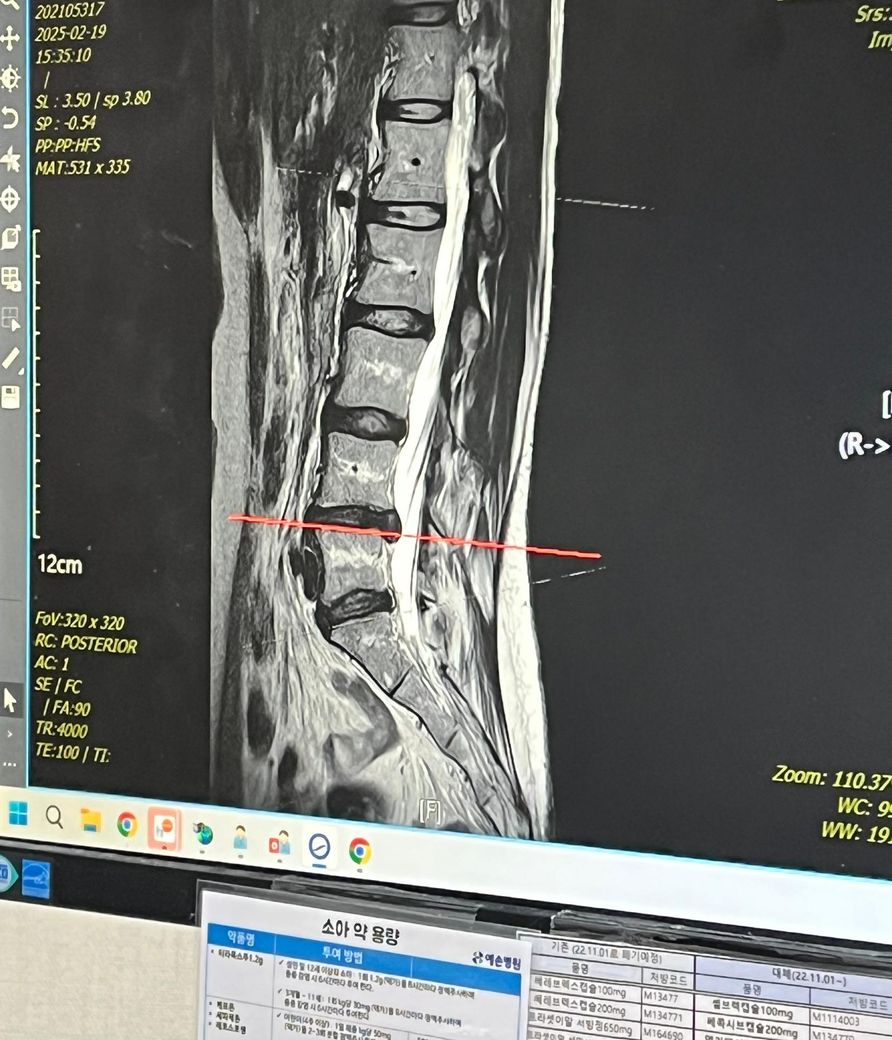

처방전엔 신경뿌리병증? 이라는데 치료 방법이 있을까요?

유명한 병원가서 mri 찍었는데 수술까진 아니로 보존치료, 신경차단술 1회 약물 몇차례 바꾸면서 내원했구요

좀 악화되어 신경성형술 1박2일 입원해 경과 지켜보기로 하는 와중에 오른쪽 허리에서 작열감 느꼈어요

그리고 사진촬영했고 원장님 오셔서 결과 듣는데 디스크가 더 나왔다고 일단 약먹고 보존치료 해보자고 해서 하는 와중에 악화되서 집 앞 대학병원으로 전원 한 상태구요

25년 11월 17일 mri 찍고 결과 보는데 오히려 디스크가 들어갔다네요